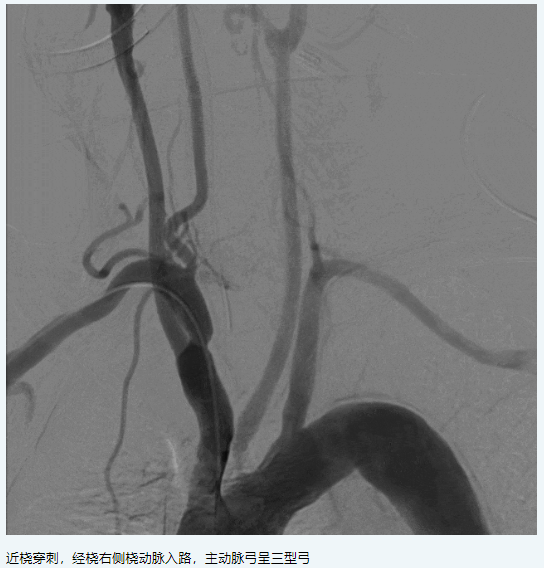

現(xiàn)病史:患者1月前因“左側偏癱,言語含糊”就診我科,溶栓后僅留有言語含糊(NIHSS評分1分)出院,出院診斷為“腦梗死,右側頸內(nèi)動脈C6段重度狹窄,高血壓病3級極高?!?,此次為進一步處理血管回診我科。

三、術前討論

擬行手術方案:右側頸內(nèi)動脈C6段狹窄球囊擴張+顱內(nèi)藥物洗脫支架植入。

手術策略:氣管插管全麻下顱內(nèi)狹窄血管介入治療。

橈動脈系統(tǒng):APEX TRA SYSTEM 7F-105cm+140cm-SIM2